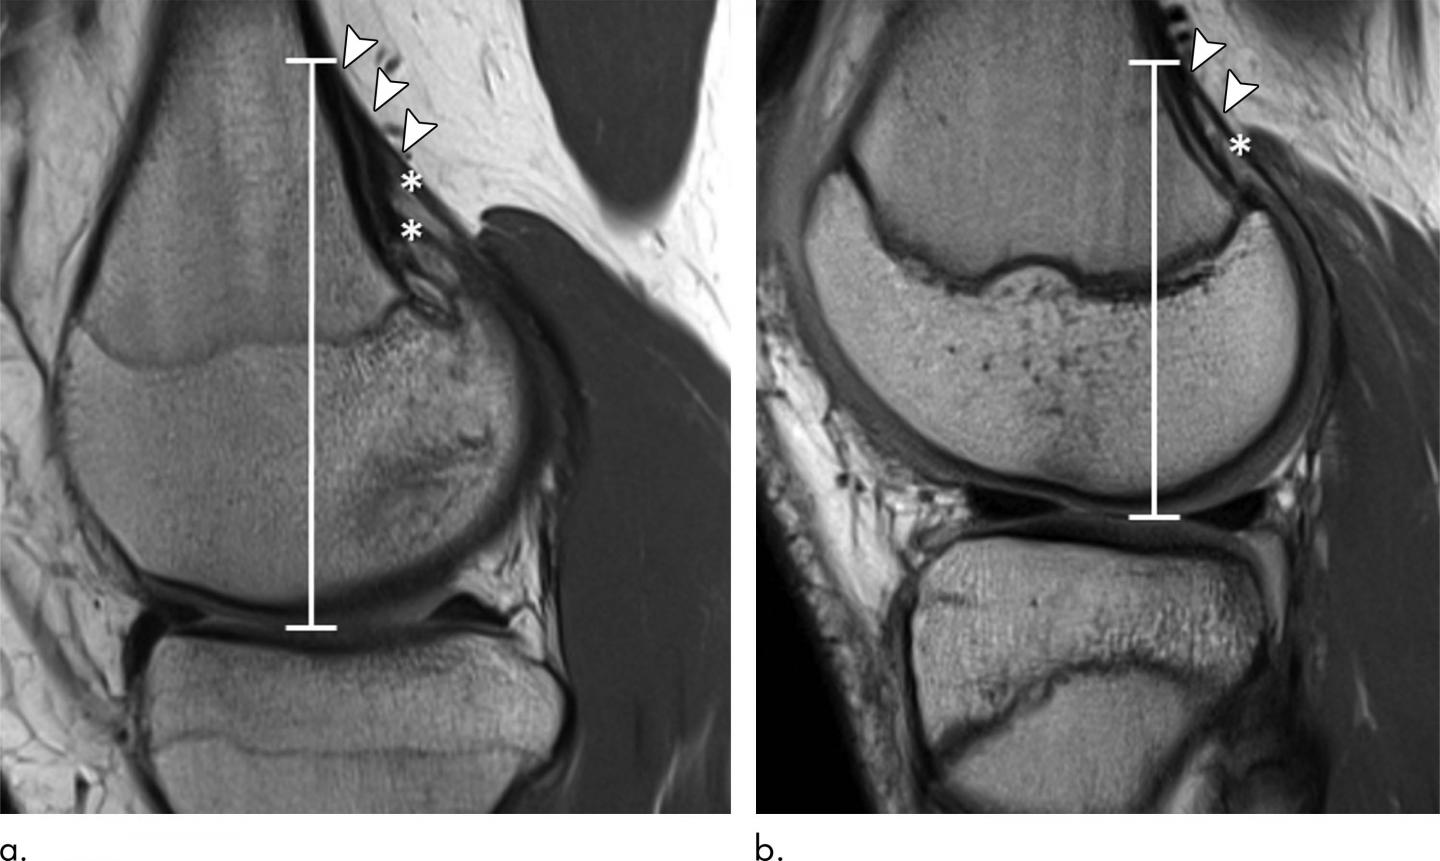

image: Sagittal proton density-weighted MRI scans in two 15-year-old female control participants without a distal femoral cortical irregularity demonstrate measurement of the tendon attachment position. Images show the craniocaudal position (white line) of the tendon attachment, which is defined as the distance from the level of the joint space to the most cranial attachment of tendon slips (arrowheads) for the (a) medial and (b) lateral head of the gastrocnemius muscle (*). Note that the tendon of the medial gastrocnemius head in a shows two prominent tendon slips.

The researchers compared the knee MRIs of 105 youth competitive alpine skiers with those of 105 controls of the same age group collected from 2014 to 2019. They looked for the presence of DFCI at two tendon-bone attachment areas: the ones between the gastrocnemius--the major muscle of the calf--and the femur, and the ones between the adductor magnus muscle of the inner thigh and the femur.

DFCIs were observed at the attachment sites of tendons, predominantly at the inside head of the gastrocnemius muscle for both skiers and controls.